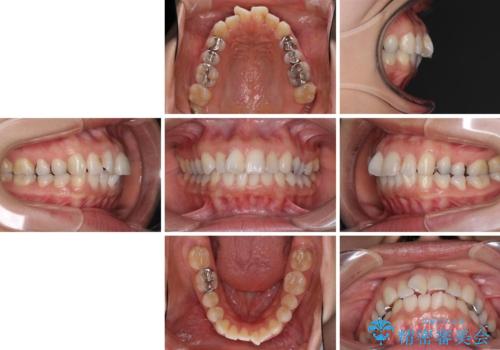

- 患者様

- 20代女性

- 矯正装置

- インビザライン

- 治療期間

- 3年2ヶ月

- 治療回数

- 10-30回

- 治療計画

- 上の前歯の捻じれと突出感を気にして来院された患者様です。

目立たない装置を希望とのことで、上顎左右第一小臼歯を抜歯し、インビザラインにて矯正治療を行うこととしました。